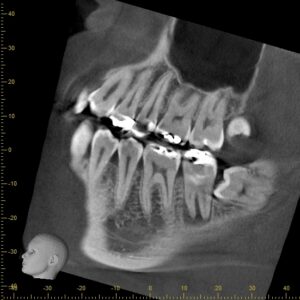

CTで根の形を確認しながら、ラバーダムとマイクロスコープを使用し根管治療を行いま

す。

治療前後で比較します。

根の周囲が白くなってきているのが分かると思います。

根管治療がうまくいき、骨が再生してきている状態です。

ここまで来れば、あとは被せ物を作製し歯が割れたりしないように補強して終了です。